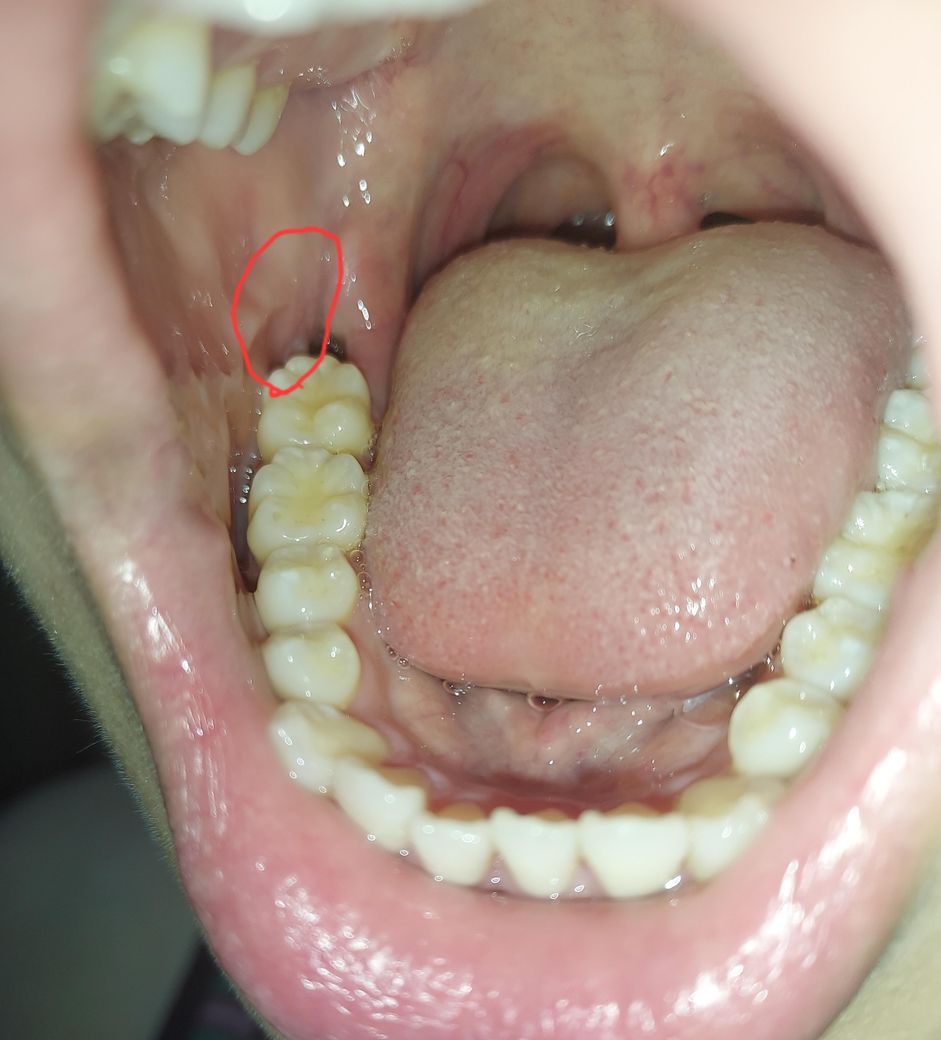

사랑니 발치 후 볼살쪽 아픔 내부감염인가요

사랑니 뺀 구멍이 아픈게 아니라 볼살쪽 안이 아파요 이런경우가 있나요ㅜㅜ

혀로 만져보면 욱씬하고요 단단?해요 염증이 있는것 같은데 나아질까요 무섭네요

• 1번 째 사진